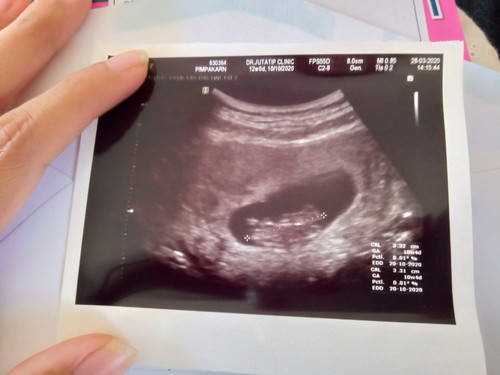

เมื่อวันที่ 28 ที่ผ่านมาได้ไปซาวน์คุณหมอบอกอายุครรภ์ 10w+4 นะคะเเต่ที่ รพ.บอก 11w+1 เราควรจะเชื่อผลซาวน์ใช่มั้ยคะเเม่ๆ